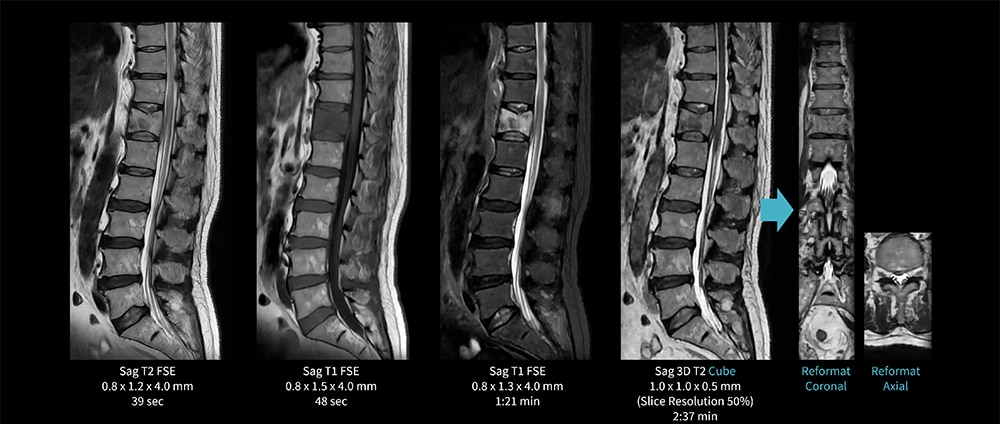

Case5 Cube/胸椎圧迫骨折

70代、男性。第12胸椎の圧迫骨折で、椎体はやや魚椎状でT1強調像で低信号T2強調像で不均一な高信号を呈する。

AIR Recon DLを併用した3D T2 Cubeを追加撮像し、多断面からの観察が可能となる。

図5 Cube を追加撮像し多段面からの観察を行う脊椎検査